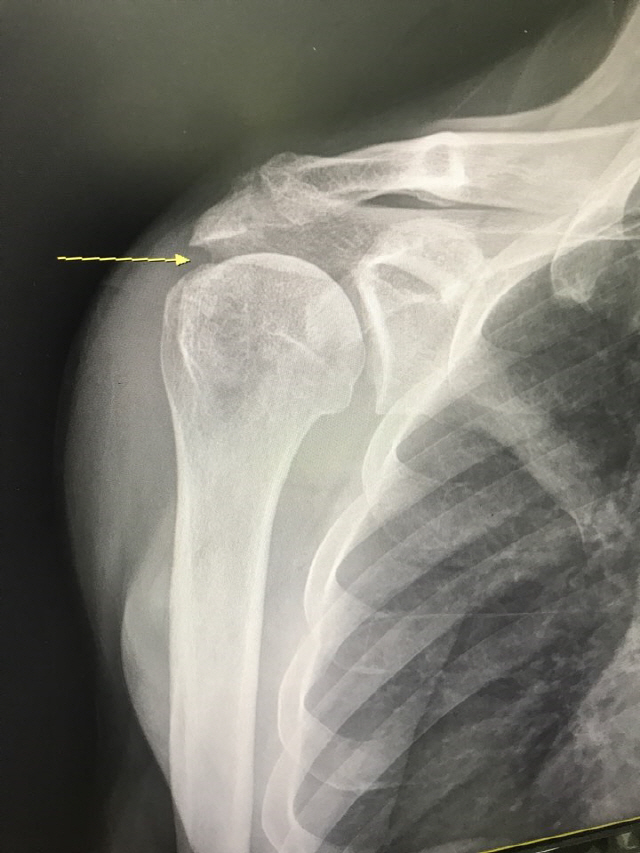

실제로 팔을 들어 근력검사와 관절범위 검사를 해보니 어깨의 근력저하가 심한 편이었다. 반대 측 팔로 아픈 팔을 받쳐 들어 올려주지 않으면 스스로 팔을 들지도 못하는 상태였다.

이처럼 어깨 힘줄이 파열되었다고 모두 수술해야 하는 것은 아니다. 첫 번째 환자처럼 어깨 힘줄이 완전히 파열되면 수술이 불가피하다. 빨리 어깨힘줄을 꿰매주지 않고 방치하면 어깨 힘줄이 안으로 말려들어가 봉합수술을 해도 결과가 나쁘거나 아예 힘줄을 새로 만들어주는 수술을 해야 하는 경우가 종종 있다.